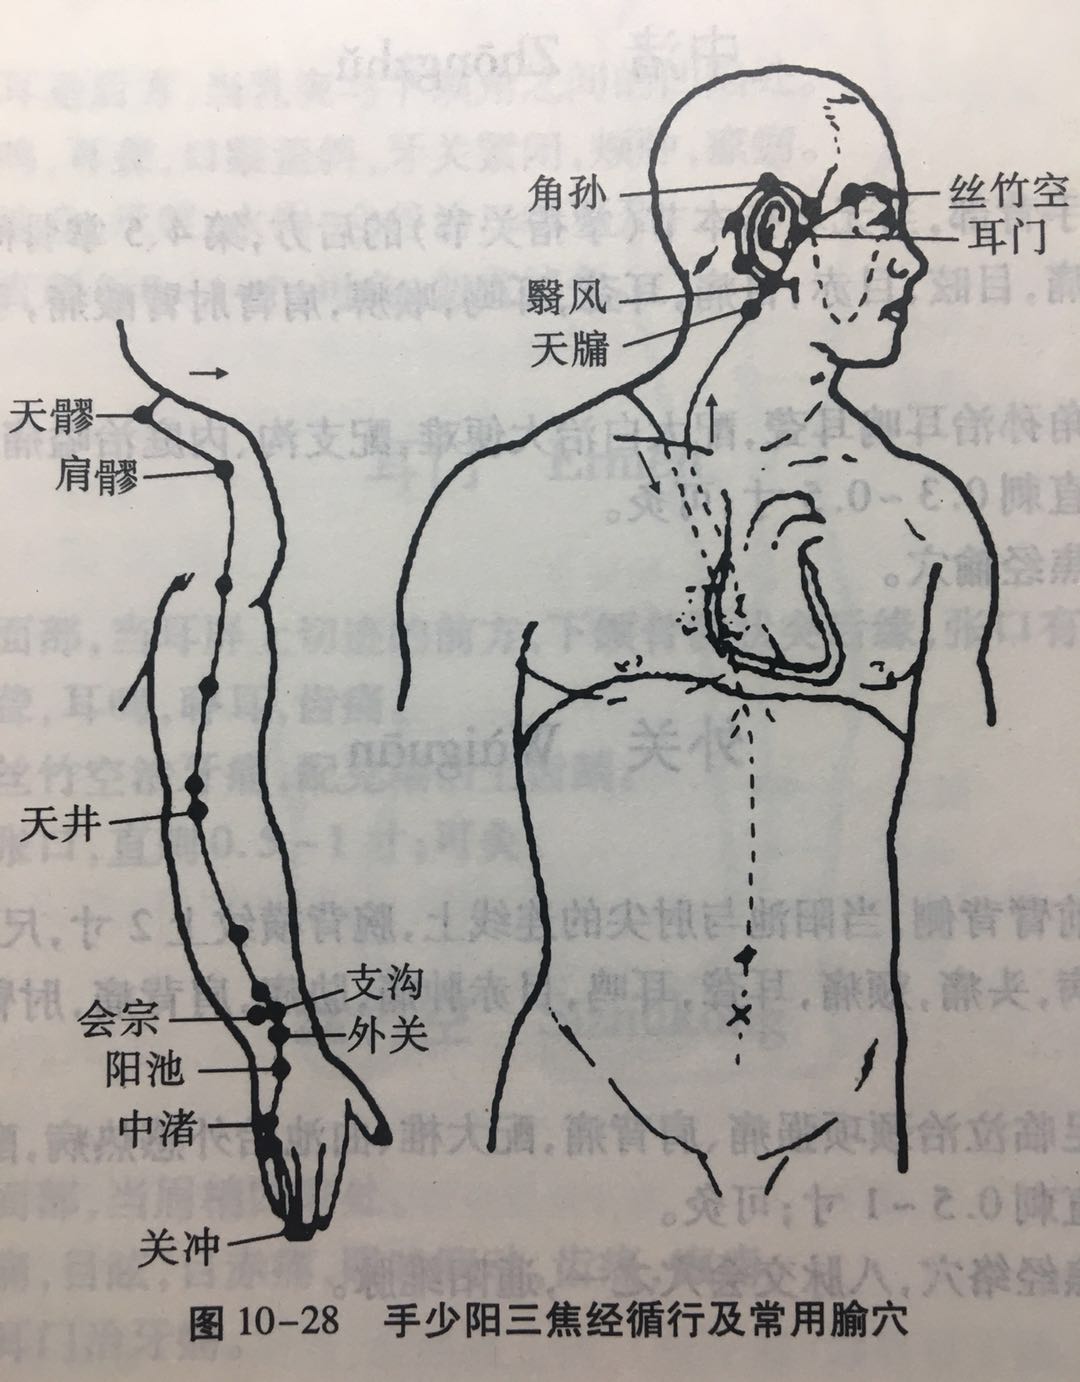

【(十)手少阳三焦经(图10-28)】

1、时辰 亥时 21 ~ 23

2、歌诀 二十三穴手少阳,关冲液门中渚旁。阳池外关支沟正,会宗三阳四渎长。天井清冷渊消泺(luò),臑会肩髎天髎堂。天牖(yǒu)翳风瘛(chì)脉青,颅息角孙丝竹空。和髎耳门听有常。

3、经脉循行 起于无名指末端(关冲)上行于第 4、5掌骨间,沿腕背、出于前臂外侧尺桡骨之间,经肘尖沿上臂外侧达肩部,交大椎,再向前入缺盆部,分布于胸中,络心包,过膈,从胸至腹,属于上、中、下三焦。

胸中支脉:从胸向上出于缺盆部,上走项部,沿耳后直上至额角,再下行经面颊部至目眶下。

耳部支脉:从耳后入耳中,出耳前,与前脉交叉于面颊部,到目外眦,与足少阳胆经相接。

4、主要病候 腹胀、水肿、遗尿、小便不利、耳聋、咽喉肿痛、目赤肿痛、颊肿、耳后、肩臂肘外侧痛等。

5、主治概要 主治侧头、耳、目、胸胁、咽喉病、热病及经脉循行部位的其他病证。

关冲

【定位】 在手无名指末节尺侧,距指甲角 0.1 寸(指寸)。

【主治】 头痛,目赤,耳聋,耳鸣,喉痹,舌强,热病,心烦。

【配伍】 配内关、人中治中暑、昏厥。

【刺灸法】 浅刺 0.1 寸,或用三棱针点刺出血;可灸。

【附注】 三焦经井穴。

中渚(zhǔ)

【定位】 在手背部,当无名指本节(掌指关节)的后方,第 4、5 掌骨间凹陷处。

【主治】 头痛,目眩,目赤,目痛,耳聋,耳鸣,喉痹,肩背肘臂酸痛,手指不能屈伸,脊膂(lǚ)痛,热病。

【配伍】 配角孙治耳鸣耳聋,配太白治大便难,配支沟、内庭治嗌(ài)痛。

【刺灸法】 直刺 0.3 ~ 0.5 寸;可灸。

【附注】 三焦经腧穴。

外关

【定位】 在前臂背侧,当阳池与肘尖的连线上,腕背横纹上 2 寸,尺骨与桡骨之间。

【主治】 热病,头痛,颊痛,耳聋,耳鸣,目赤肿痛,胁痛,肩背痛,肘臂屈伸不利,手指疼痛,手颤。

【配伍】 配足临泣治颈项强痛、肩背痛,配大椎、曲池治外感热病,配阳陵泉治胁痛。

【刺灸法】 直刺 0.5 ~ 1 寸;可灸。

【附注】 三焦经络穴,八脉交会穴之一,通阳维脉。

支沟

【定位】 在前臂背侧,当阳池与肘尖的连线上,腕背横纹上 3 寸,尺骨与桡骨之间。

【主治】 暴喑(yīn),耳聋,耳鸣,肩背酸痛,胁肋痛,呕吐,便秘,热病。

【配伍】 配天枢治大便秘结,配双侧支沟治急性腰扭伤、胁痛。

【刺灸法】 直刺 0.5 ~ 1 寸;可灸。

【附注】 三焦经络穴。

肩髎

【定位】 在肩部,肩髃(yú)后方,当臂外展时,于肩峰后下方呈现凹陷处。

【主治】 臂痛,肩重不能举。

【配伍】 配天宗、曲垣(yuán)治疗肩背疼痛;配肩井、天池、养老治上肢不遂、肩周炎。

【刺灸法】 直刺 0.5 ~ 1 寸;可灸。

翳(yì)风

【定位】 在耳垂后方,当乳突与下颌角之间的凹陷处。

【主治】 耳鸣,耳聋,口眼歪斜,牙关紧闭,颊肿,瘰疬。

【配伍】 配地仓、承浆、水沟、合谷治口噤不开。

【刺灸法】 直刺 0.8 ~ 1 寸;可灸,勿直接灸。

耳门

【定位】 在面部,当耳屏上切迹的前方,下颌(hé)骨髁(kē)状突后缘,张口有凹陷处。

【主治】 耳聋,耳鸣,聤(tíng)耳,齿痛。

【配伍】 配丝竹空治牙痛,配兑端治上齿龋(qǔ)。

【刺灸法】 张口,直刺 0.5 ~ 1 寸;可灸。

丝竹空

【定位】 在面部,当眉梢凹陷处。

【主治】 头痛,目眩,目赤痛,眼睑瞤(rún)动,齿痛,癫痫。

【配伍】 配耳门治牙痛。

【刺灸法】 平刺 0.5 ~ 1 寸。不宜灸。